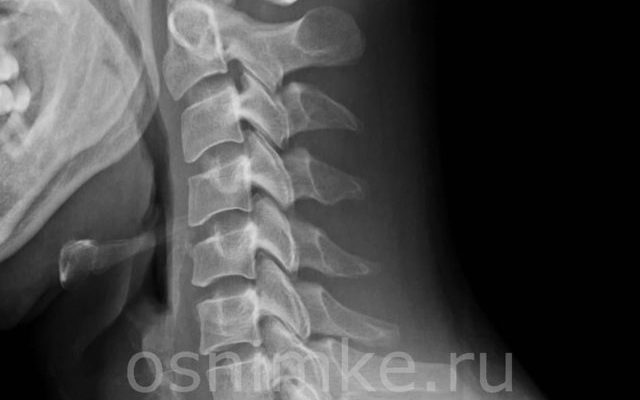

Рентгенологическое исследование позвоночника чрезвычайно важно при диагностике заболеваний опорно-двигательного аппарата, нервной и сердечно-сосудистой систем. При обследовании шейного отдела позвоночника это имеет особое значение, поскольку на рентгенограмме шеи выявляются патологии, связанные с головным мозгом, церебральными сосудами.

- Получив результаты обследования, врач внимательно анализирует, что показала рентгенография шейного отдела позвоночника. По результатам сканирования в этом отделе можно обнаружить неровности или особенности:

- Последствия травматического повреждения шейного отдела позвоночника. Это могут быть вывихи, ушибы, смещения, переломы;

- трансформация позвоночника в шейном отделе;

- Гипертрофии, образующиеся вокруг позвоночной артерии в области первого шейного позвонка — это аномалия Киммерле. Данная патология является врожденной, поэтому ее можно диагностировать даже у маленьких детей. При сдавливании позвоночной артерии нарушается кровоснабжение;

- дегенеративно-дистрофические изменения, такие как шейный остеохондроз;

- воспалительные патологии, провоцирующие раздражение межпозвоночного нерва. Это состояние вызывает шейный радикулит;

- наличие аномального костного образования, такого как клиновидный позвонок;

- искривление позвонков из-за разрастания кости. К таким патологиям относятся спондилез;

- Остеопороз шейного отдела позвоночника;

- нарушение обмена веществ;

- кифоз в шейно-грудном отделе;

- новообразования, расположенные в шейном отделе позвоночника;